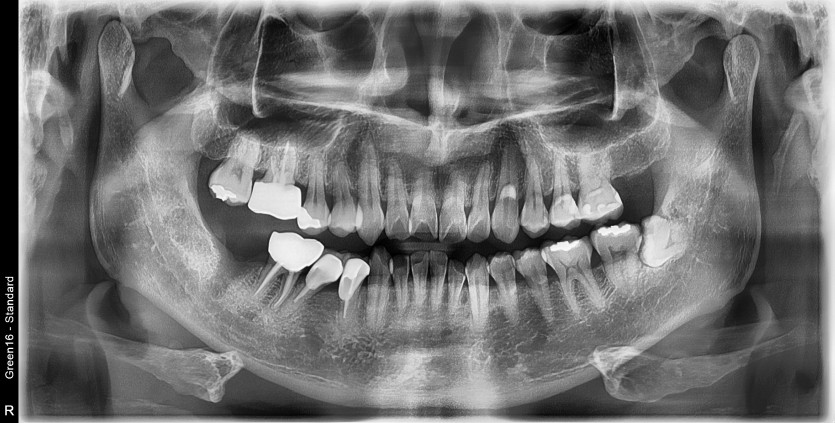

#38 사랑니 발치

구강외과 전문의가 당일 발치하였습니다.